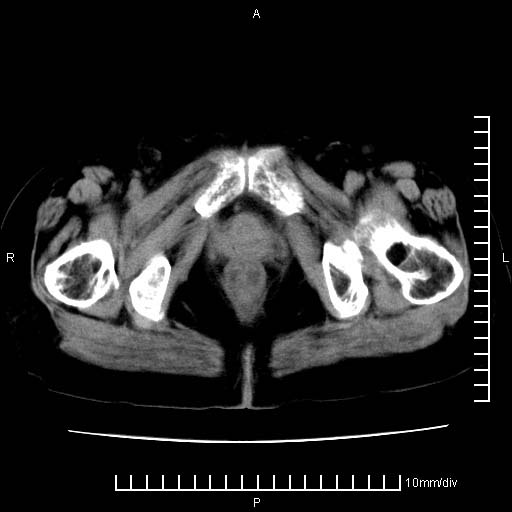

下腹疼痛2月,加重并呕吐2天,下腹压痛,反跳痛。白细胞1万2.

下腹至盆腔较大包块,与邻近肠管关系密切,下腹疼痛2月,加重并呕吐2天,下腹压痛,反跳痛。白细胞1万2.

由于没有做肠道准备很难分清是哪根肠管,但看位置考虑为升结肠回盲部的问题,我首先考虑化脓性阑尾炎,不除外结肠癌合并感染化脓。建议做增强进一步明确。

补充:道格拉斯腔内有积液,且密度较高,显然提示有感染。

考虑右侧卵巢囊肿伴感染可能性大。

附件实性肿块有坏死 考虑卵巢癌

盆腔脓肿伴盆腔积液

来源于附件占位—多考虑:卵巢癌!

不知道大家可要注意下腹腔小肠旁不规则结节状灶,部分钙化,是否要考虑小肠腺癌.盆腔包块可能考虑脓肿.

考虑卵巢恶性肿瘤;盆腔积液。